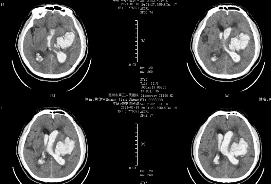

術(shù)后ct

神經(jīng)外科文世宏教授團(tuán)隊(duì)使用手術(shù)機(jī)器人精準(zhǔn)定位血腫后,在神經(jīng)內(nèi)鏡下實(shí)施顱內(nèi)血腫清除術(shù),為李大爺成功清除顱內(nèi)血腫,解除了顱內(nèi)壓增高,同時(shí)對(duì)腦組織和顱神經(jīng)進(jìn)行有效的保護(hù)。手術(shù)十分順利,術(shù)后醫(yī)護(hù)人員將李大爺送到ICU(重癥監(jiān)護(hù)室),給予止血,祛痰,抗炎、營(yíng)養(yǎng)神經(jīng)等治療。